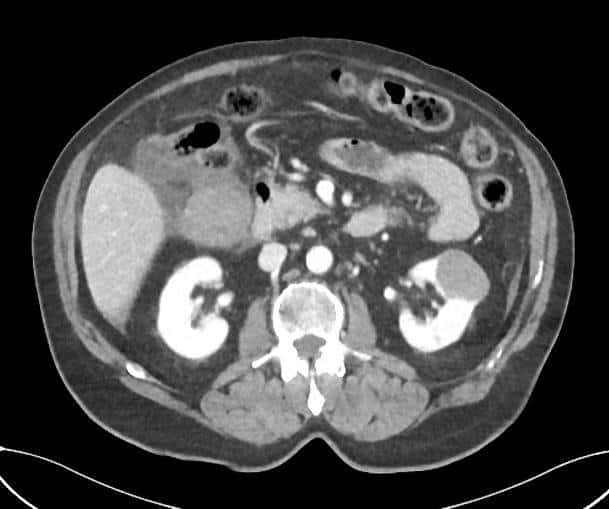

Vỡ túi mật

» Thông tin: Nam giới – 80 tuổi.

» Lâm sàng: Chấn thương.